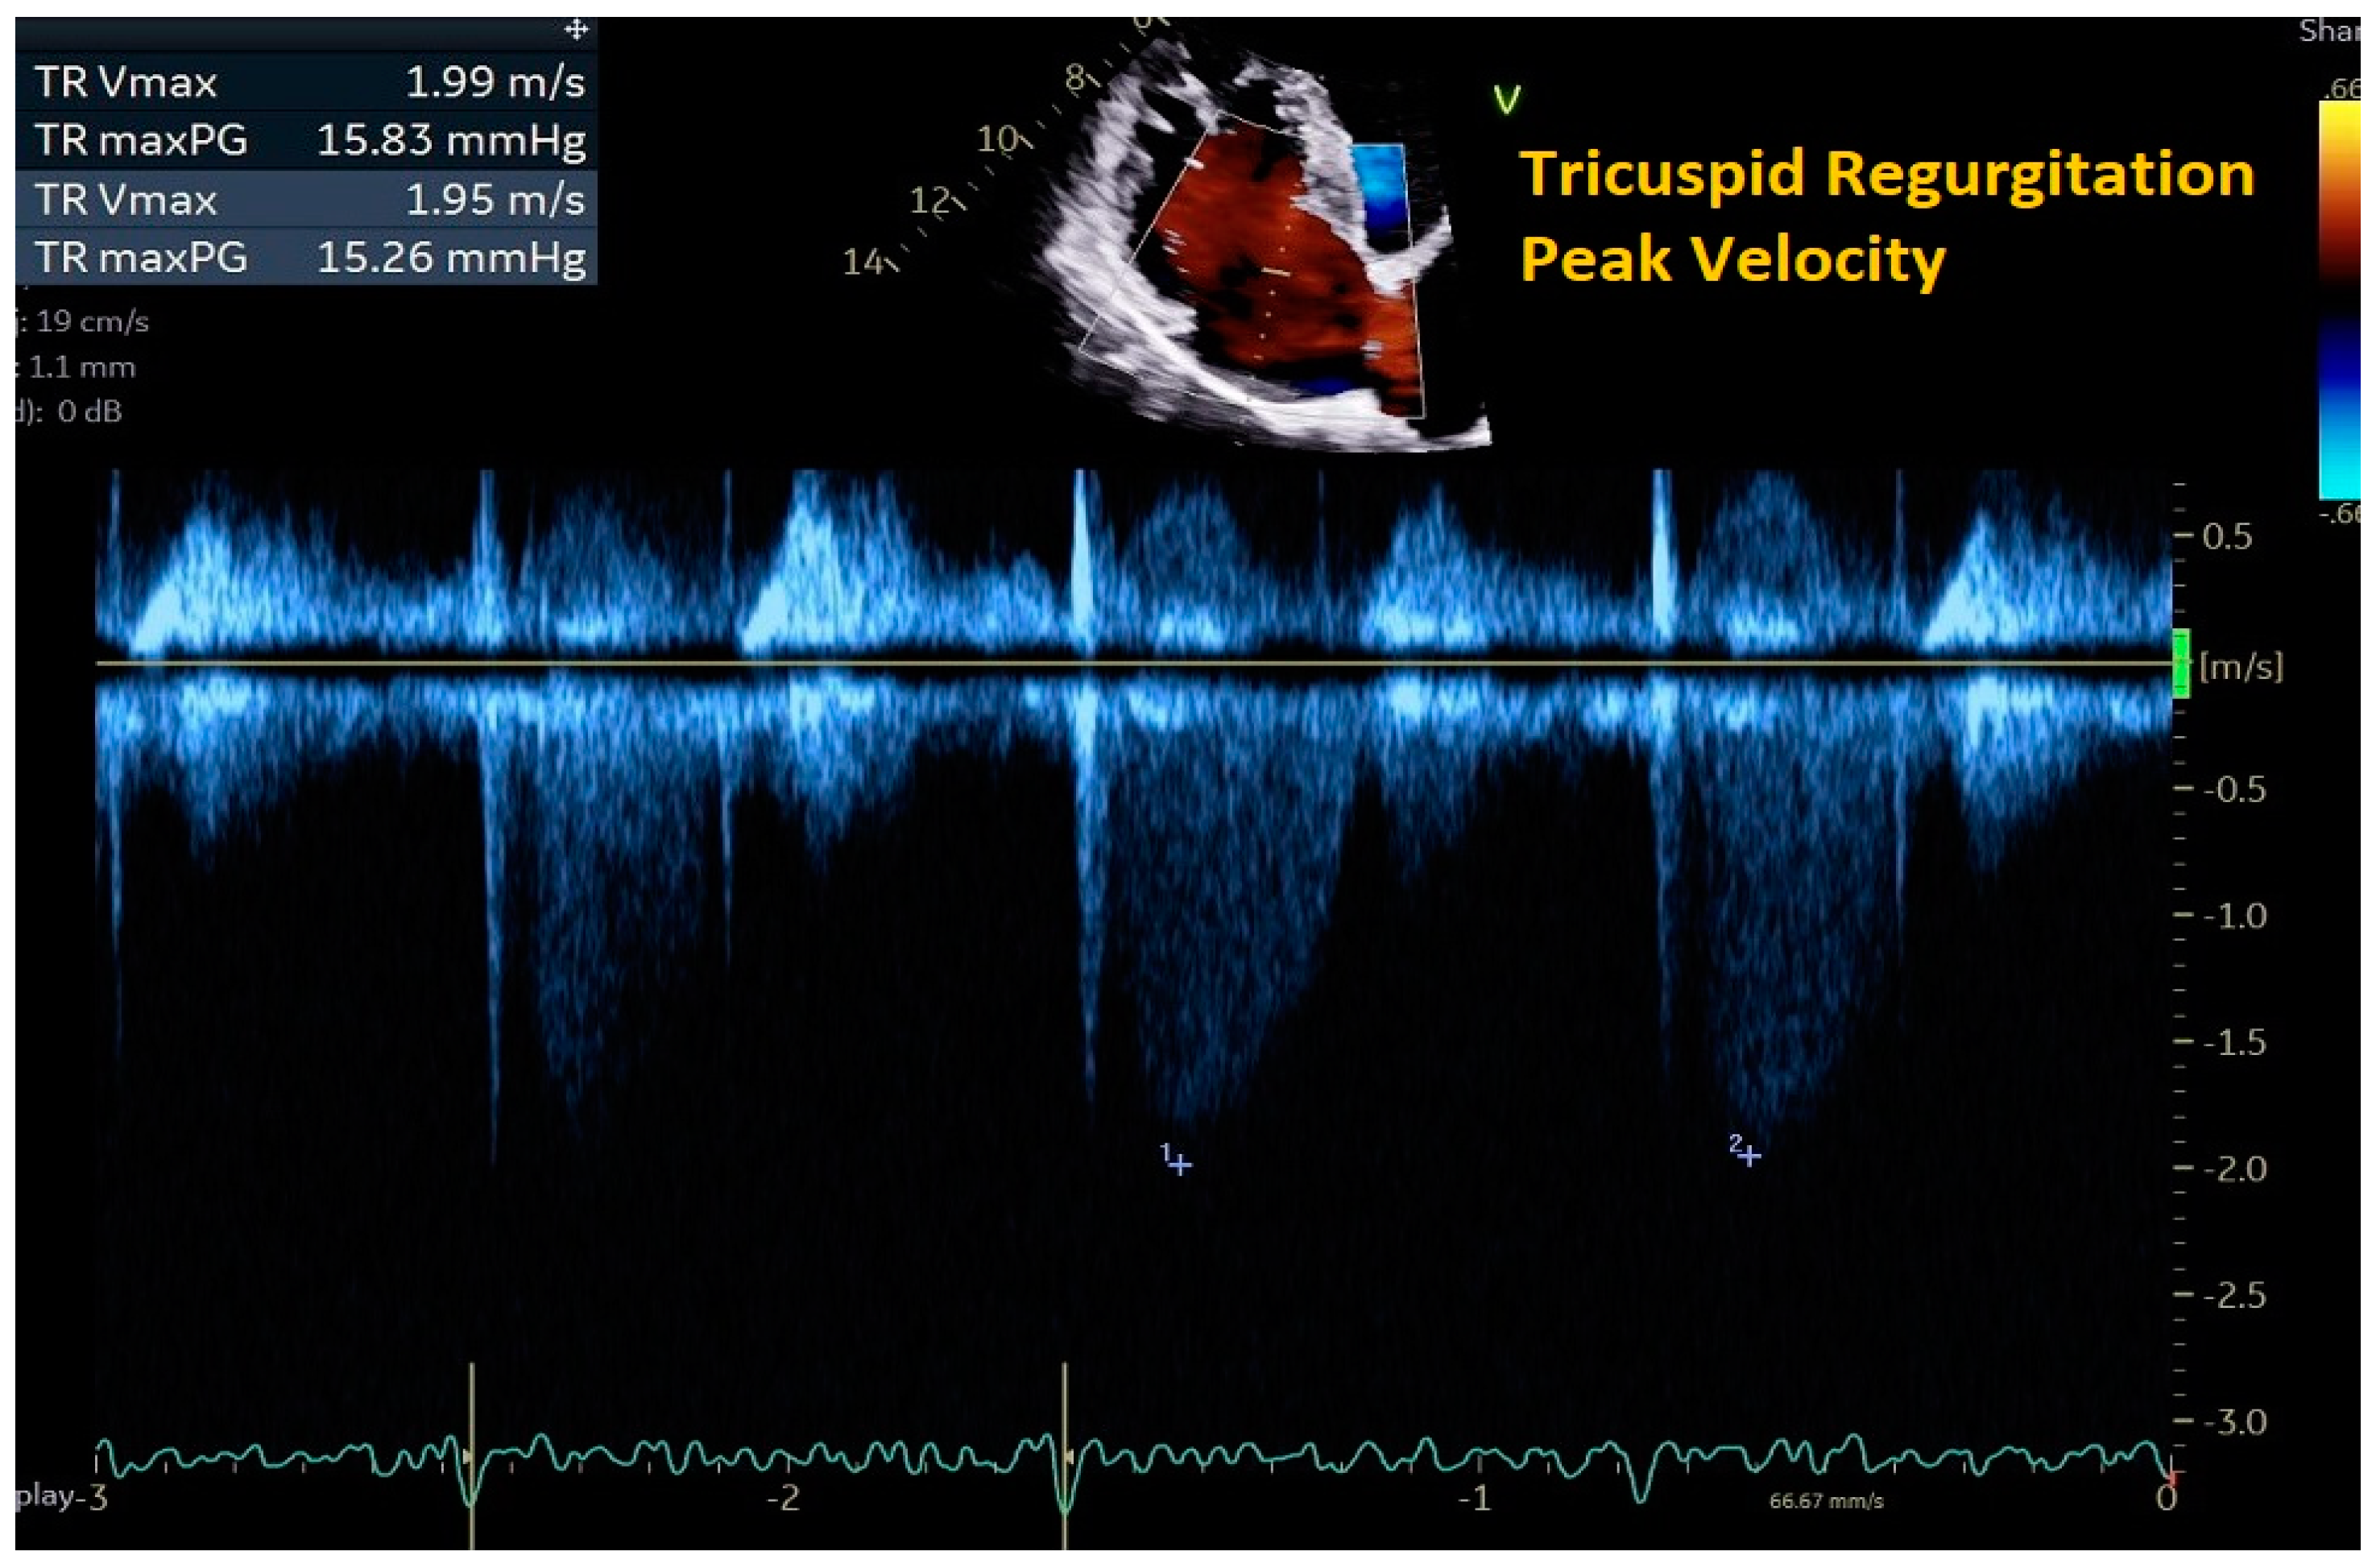

2. Cardiac Ultrasound

- Rao, S.D.; Adusumalli, S.; Mazurek, J.A. Pulmonary Hypertension in Heart Failure Patients. Card. Fail. Rev. 2020, 6, e05. [Google Scholar] [CrossRef] [PubMed]

| Peak velocity of the TR jet | ≤2/8 m/s |

|

| |

| Estimated PASP using TR jet plus estimated RAP from IVC assessment | ≤35 mmHg |

|

| |